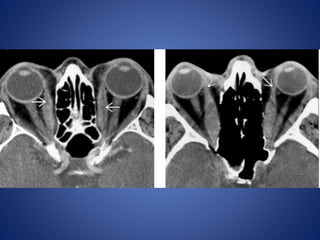

Retinal detachment

Choroidal detachment

Choroidal detachment is accumulation of blood or fluid in supra

choroidal space between choroid and sclera, so collection extend

circumferentially along the entire supra choroidal space ,

configuration is lentiform shaped along medial as well as lateral wall

of globe, choroid bulging medially on either side giving so called

kissing choroid sign.

Anteriorly extend upto ciliary bodies and posterior limit formed by

anchoring effect of short posterior ciliary arteries and nerves

preventing convergence of detached choroidal leaves to a single

point.

Configuration of collectionis cresent shaped or V shaped on axial sections. Limbs of V represent detached leaves of retina converging towards optic disc represent the apex of V. Collection anteriorly extend upto ora serrata represent anterior limit due to normal anterior attachment of retina. Retinal detachment

Choroidal detachment Choroidal detachmentis accumulation of blood or fluid in supra choroidal space between choroid and sclera, so collection extend circumferentially along the entire supra choroidal space , configuration is lentiform shaped along medial as well as lateral wall of globe, choroid bulging medially on either side giving so called kissing choroid sign. Anteriorly extend upto ciliary bodies and posterior limit formed by anchoring effect of short posterior ciliary arteries and nerves preventing convergence of detached choroidal leaves to a single point.